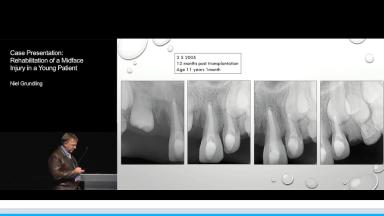

A 9 year old girl sustained severe soft tissue and facial bone injuries when a brick was thrown through the window of the vehicle in which she was travelling. The injuries included laceration and abrasion of the upper lip, nose and glabella, degloving of the midface, fracture of the frontal bone, nasal septum, nasal bones, nasal cartilage, dentoalveolar fracture and avulsion of teeth 12 and 11 and fracture of the incisal edges of the lower insicors.

The multidisciplinary approach to the management and rehabilitation of this young girl is presented which includes the initial, intermediate and final phases of treatment.